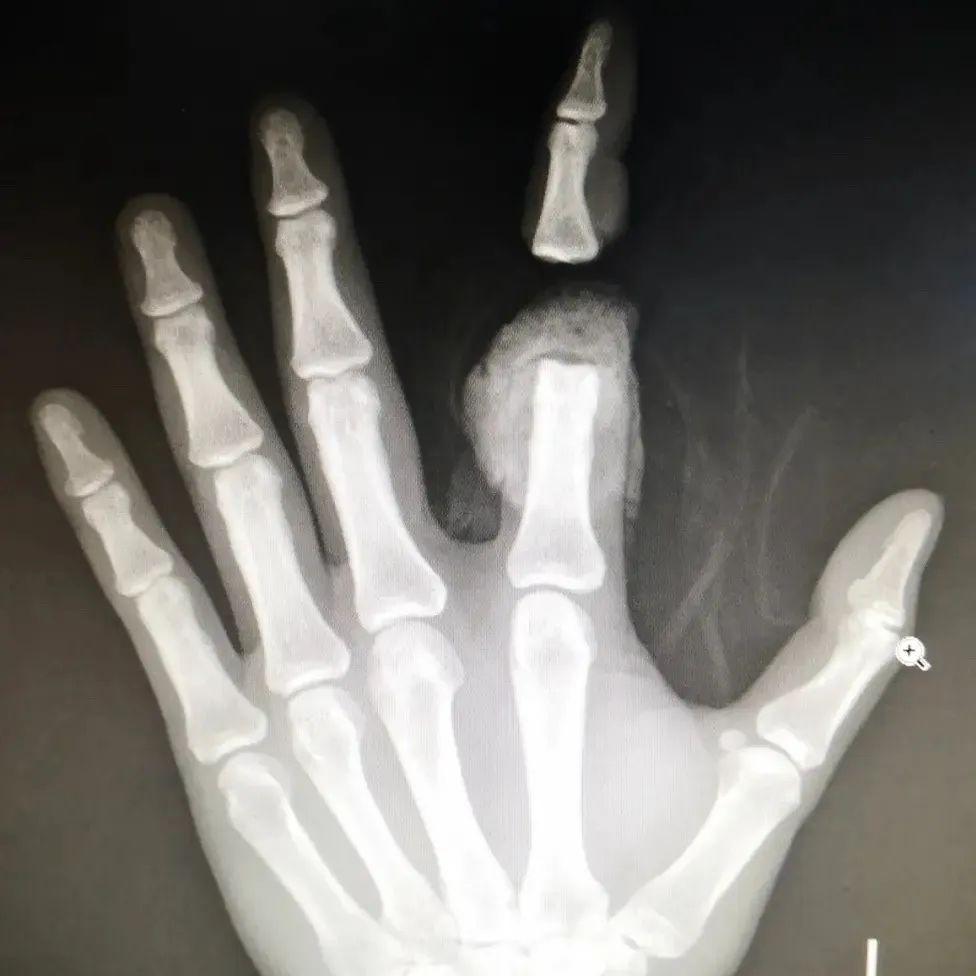

近日,患者强先生不慎被电锯割伤,导致食指自第一指节处完全离断,被紧急送至西安市长安区医院急诊科。患者伤情危重,创面极不规整,大量出血,并自行携带有离断指体。面对这一紧急情况,医院立即启动创伤救治绿色通道,急诊科及创伤病区团队紧密协作,成功为强先生实施断指再植手术,保住了其手指功能。目前,患者断指已确认成活,正处于功能恢复阶段。

患者抵达急诊科后,医护团队对其生命体征和伤情进行了快速、全面的评估,诊断为左手食指完全性离断伤,创面污染挫伤严重。对于离断指体而言,6-8小时内恢复指体血运是提高成活率的关键。团队争分夺秒安排各项术前检查,并同步通知创伤病区显微外科团队做好急诊手术准备。多部门高效联动,为后续手术争取了宝贵时间。

手术室内,一场与时间赛跑的精密手术在高倍显微镜下展开。麻醉成功后,团队首先对伤指进行彻底清创,对接骨骼,并细致修复受损肌腱。随后开始吻合细如发丝的神经与血管。然而,术中探查发现,由于电锯伤的特性,创面边缘极不规整,离断指体断端有一长段血管挫伤严重,无法直接吻合。面对这一突发情况,显微外科组当即调整手术方案,在与家属充分沟通后,决定实施“移花接木”——即从患者腕部选取管径合适的血管移植,以修复损伤血管,最终挽救断指。

手术由蔺秋麇主任与吕蒙医生等团队成员协作进行,蔺秋麇主任负责清除残肢异物,在保护缺损的血管神经的同时彻底清创、整理修复离断食指,使用骨圆针固定指关节骨骼后,探查血管,由深及浅依次修复关节囊、伸屈肌腱等。吕蒙医生则负责“移花接木”,将取自腕部的浅静脉移植桥接至食指双侧指固有动脉并进行精细吻合。经过3小时的紧张手术,断指再植顺利完成,术中血管通血良好。